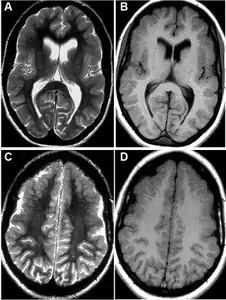

Magnetic resonance imaging

MRI is one of the best techniques that can detect the lesions in the brain of the FCMS that some of the times are missed by just using a Computer-Tomography Scan. Also, this type of imaging can reveal right frontal lobes contusions encompassing the anterior operculum, the premotor area, and the association area.[10]